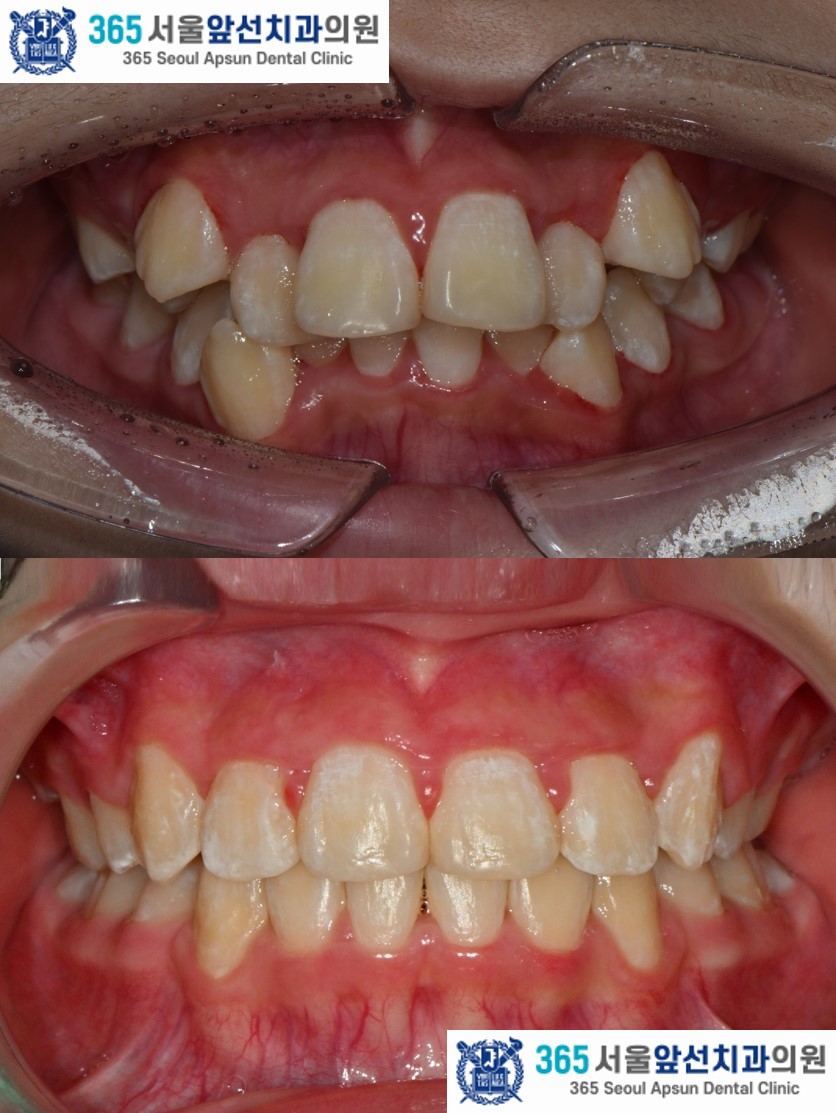

돌출입과 덧니를 고민으로 내원하신, 10대 청소년 환자 분의 증례를 소개드리겠습니다. 촬영일시 : 2024.05.21. / 2026.03.28 치료 전, 심한 공간 부족으로 송곳니 덧니와 앞니의 비뚤비뚤하게 겹친 치열이 관찰됩니다. 상악 치열의 경우 7.0mm의 공간 부족, 하악 8.5mm의 공간 부족이 있습니다. 임상적 및 방사선학적 검사 결과 위턱의 돌출과 아래턱의 후퇴를 동반한 2급 골격과, Angle씨 분류 치성 2급 부정교합 및 과도한 수직 및 수평 피개(과개교합)과 심한 총생으로 진단되었습니다. 치아 크기에 비해 악궁의 크기가 작은 부조화도 있으셔서, 비발치 교정보다는 발치 교정으로 치료하는 것이 적합합니다. 따라서, #14,24,34,44 제1소구치 치아의 발치와 전체 치열의 고정식 교정장치 치료(Clippy-C), 상악 교정용 미니임플란트를 이용한 추가적 치열의 후방이동을 계획하였습니다. 촬영일시 : 2024.05.21. 치료 후의 모습입니다. 2024년 6월 5일 치료를 개시하여 2026년 3월 28일에 교정치료를 종료하였으며 총 1년 8개월의 치료기간이 소요되었습니다. 치열이 가지런하게 배열되면서 후방이동 되어 Angle씨 분류 치성 1급 관계가 달성되었고, 얼굴형 또한 돌출입의 개선과 더불어 입술 폐쇄가 개선되었습니다.

촬영일시 : 2026.03.28. 치료 전과 치료 후의 비교입니다. 돌출감이 감소하고 입술 폐쇄가 개선되어 옆모습이 크게 개선된 매우 만족스러운 치료 결과였습니다.